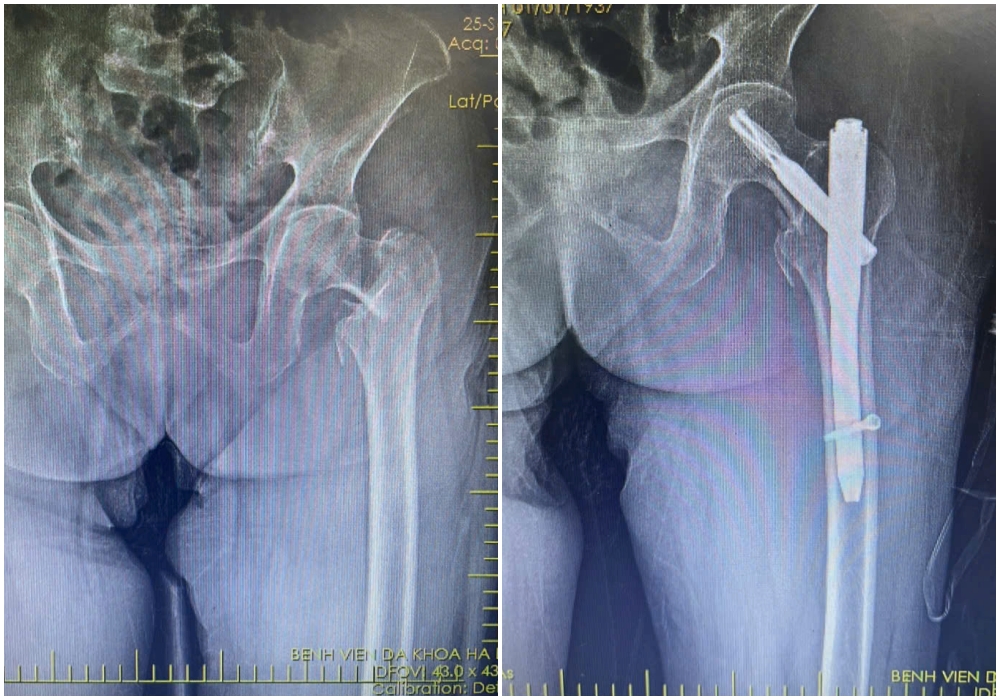

Hình ảnh X-quang gãy liên mấu chuyển xương đùi trái của bệnh nhân H (88 tuổi) được kíp mổ phẫu thuật kết hợp xương ít xâm lấn.

Hình ảnh X-quang gãy liên mấu chuyển xương đùi phải của bệnh nhân N (87 tuổi) được kíp mổ phẫu thuật kết hợp xương ít xâm lấn